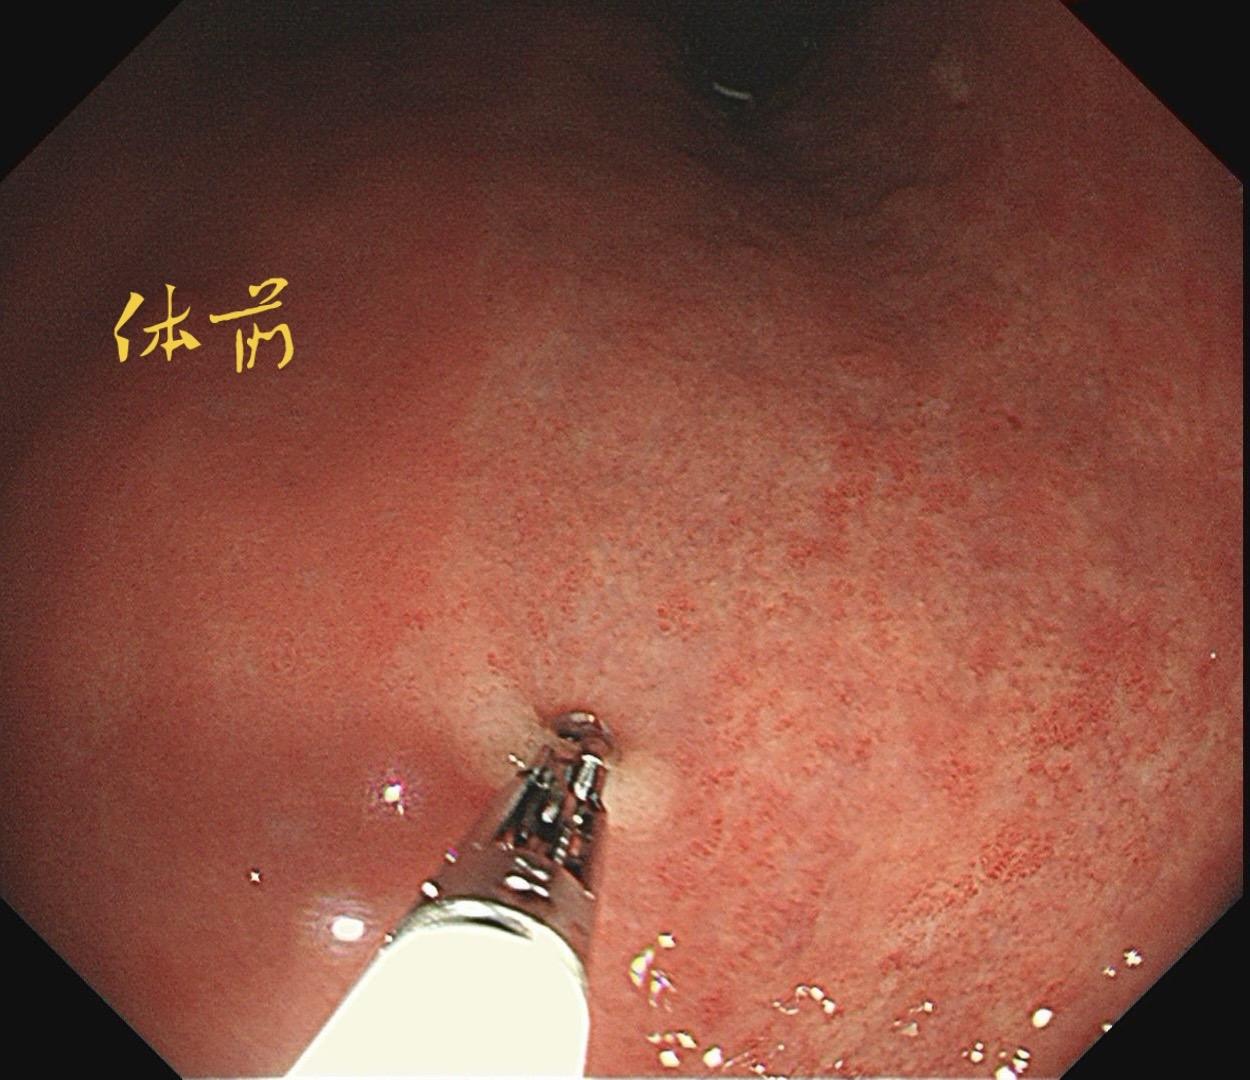

男,61岁,胃巨大褪色调病变。答案在最后一张图片,你猜对了吗? 患者因上腹部饱胀行胃镜检查,Hp阴性背景,胃窦至贲门下见一巨大褪色调病变,边界清晰,病变相对表浅,未见明显溃疡及隆起,胃壁较柔软,充气顺应性佳,予多点活检确诊,拟外科手术行全胃切除。做这么多年胃镜,还是第一次遇到这样的……